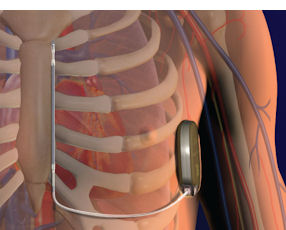

Implantable cardioverter defibrillators—including one developed in Orange County—could be in line for higher Medicare payments.

Implantable cardioverter defibrillators are used to prevent heart attacks.

The agency is proposing a 6.4% increase for implantable cardioverter defibrillators for the 12 months starting Oct. 1. The devices have been tabbed for the highest increase among cardiovascular products.

Analysts with Boston-based Leerink Swann LLC called the proposed increase a “positive” for Boston Scientific Corp., which got the S-ICD defibrillator in an acquisition of San Clemente-based Cameron Health Inc. a year ago. Also expected to benefit from higher Medicare payments are two Minnesota-based medical device makers with Orange County operations—Medtronic Inc. and St. Jude Medical Inc.

The analysts’ report noted that Medicare would pay on average a base rate of $35,934.11 for implantable cardioverter defibrillator implants. Medicare currently pays an average of $33,759.22 for such implants.

Boston Scientific’s S-ICD is considered a breakthrough in its market because it doesn’t have lead wires that could fracture and cause other problems for patients.